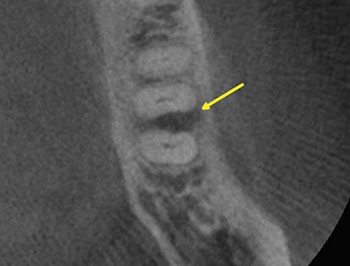

Case 9: A crack ‘seen’ on CBCT

This patient requested a second opinion after an endodontist advised them to extract tooth #14. The extraction was recommended because the endodontist believed that a VRF was visible on the palatal root on the CBCT. The previous NSRCT and metal post might have given more supportive context for the argument, but the crack “seen” on the CBCT was used to make the diagnosis of VRF.

When radiopaque dental materials, such as obturations or posts, are present in the same plane as the root, CBCT is not effective in identifying VRF. Reconstruction artifacts often present as dark lines that can be misinterpreted as cracks. Furthermore, posts generally look larger than they really are on the CBCT and often appear to perforate root surfaces when they are not. This tooth was not cracked. The periradicular tissues healed completely following nonsurgical re-treatment.

Endodontic Root Fracture Case Series

Fig.32: Preop PA.

Fig.33: Preop CBCT AX.

Fig. 34: Preop CBCT COR.

Fig. 35: Preop CBCT SAG.